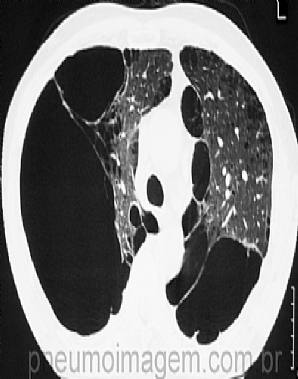

Veja imagens de DPOC no PneumoImagem, clique aqui.